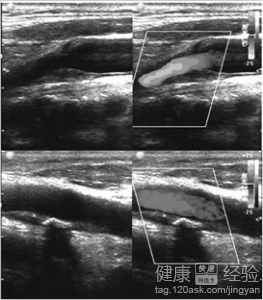

頸動脈硬化如何檢查

概 述 頸動脈的硬化多表現為一些局部的症狀,也是頸動脈及外部動脈合力作用下的產物,會形成一個病區,